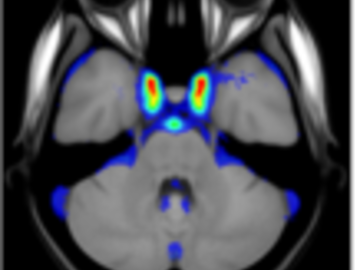

A statistical atlas of cerebral arteries

Magnetic resonance angiography (MRA) can capture the variation of cerebral arteries with high spatial resolution. These measurements include valuable information about the morphology, geometry, and density of brain arteries, which may be useful to identify risk factors for cerebrovascular and neurological diseases at an early time point. However, this requires knowledge about the distribution and morphology of vessels in healthy subjects. the statistical arterial brain atlas described in this work is a free and public neuroimaging resource that can be used to identify vascular morphological changes. The atlas was generated based on 544 freely available multi-center MRA and T1-weighted MRI datasets. the arteries were automatically segmented in each MRA dataset and used for vessel radius quantification. The binary segmentation and vessel size information were non-linearly registered to the MNI brain atlas using the T1-weighted MRI datasets to construct atlases of artery occurrence probability, mean artery radius, and artery radius standard deviation. This public neuroimaging resource improves the understanding of the distribution and size of arteries in the healthy human brain.

The statistical atlas consists of four image files in the niftii format and in MNI reference space (0.5 mm^3). These files include the TOF MRA average atlas (tofAverage.nii.gz), the vessel probability atlas (vesselProbabilities.nii.gz [in %]), the mean artery radius atlas (vesselRadius.nii.gz [in mm]), and the standard deviation of the artery radius atlas (vesselRadiusStd.nii.gz [in mm]). All images are saved using float values. The TOF MRA and T1-weighted datasets used for atlas generation can be downloaded from the original sources.